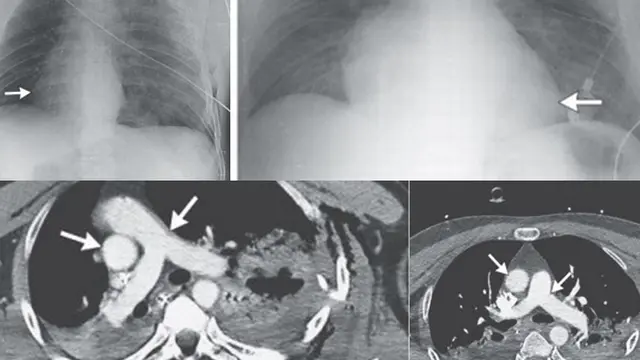

Jantung Berpindah tempat

2014 ini, seorang pria Italia berusia empat puluhan tahun yang tak disebutkan namanya menunjukkan gejala tak biasa di rumah sakit usai mengalami kecelakaan sepeda motor. Dokter mengalami kesulitan mendengar detak jantungnya dengan baik. Kabarnya, jantung bagian kanan menunjukkan abnormal jantung yang disebut dekstrokardia. Biasanya, kondisi ini dialami mereka yang cacat lahir. Namun, uniknya kejadian ini dialami karena disebabkan oleh kecelakaan.

Istilah sederhananya, jantung tidak berada di posisi yang tepat sehingga tidak memompa dengan benar.